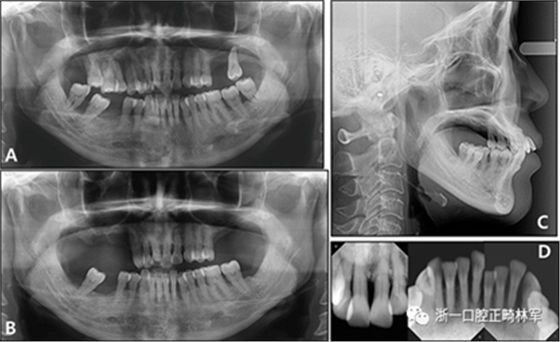

全景X線片顯示了牙槽骨支持的整體下降和下頜左側(cè)側(cè)切牙區(qū)廣泛的骨質(zhì)喪失。頭影測量分析表明是具有正常垂直面形,上頜切牙唇向錯位以及與Rickett‘s E線相關(guān)的上唇前凸的骨性I類關(guān)系(圖3和4;表II)?;颊弑辉\斷為骨骼I類錯合畸形,伴有慢性中度牙周炎和多顆牙齒缺失。

圖3. 治療前X線片:A,牙周治療前的全景X光片; B,牙周治療后的全景X光片; C,側(cè)位X線片; D,根尖片。

圖4. 治療前的投影測量